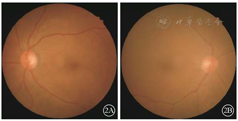

患者男,63岁。因视物不清伴夜视力下降于2017年8月3日到吉林大学第二医院眼科就诊。既往无眼科病史,无高血压、糖尿病病史。2年前因胆管癌行胆汁外引流手术。眼科检查:右眼视力0.2,左眼视力0.7,矫正均不能提高。右眼、左眼眼压分别为16、17 mmHg (1 mmHg=0.133 kPa )。双眼结膜干燥,颞侧及鼻侧球结膜可见小片状睑裂斑及实性块状隆起,球结膜颜色偏黄,转动见皱褶;上睑板腺可见部分阻塞(图1)。除晶状体略微混浊外,其余眼前节检查正常。眼底检查,双眼视盘边界清楚、颜色淡,视网膜血管走形大致正常,黄斑中心凹反光欠佳(图2)。双眼OCT检查未见异常。全视野ERG检查,双眼暗适应视杆细胞反应a、b波波形消失,暗适应最大反应a、b波振幅明显降低;明适应最大反应a、b波振幅轻度降低(图3)。结合病史及相关检查结果考虑维生素(V)A缺乏症,建议患者行微量元素检测。结果显示,血清VA含量<0.03 mg/L(正常值>0.3 mg/L),VE含量3.4 mg/L(正常值5.5~ 17.0 mg/L)。诊断:VA缺乏症、结膜干燥症、睑板腺功能异常、双眼白内障。请外科及营养科会诊,考虑患者VA缺乏系胆汁外引流导致吸收障碍所致。综合全身状况建议患者每天摄入VA 4000国际单位并回收自体胆汁,同时辅用人工泪液以缓解干眼症状,随诊。2017年9月1日患者复诊,主诉视力明显好转。右眼视力0.4,左眼视力0.9,矫正均不能提高。干眼及睑板腺功能障碍有所好转。眼底改变同治疗前。全视野ERG检查示a、b波形均恢复正常(图4)。血清VA、VE含量恢复正常水平,分别为0.38、4.2 mg/L。